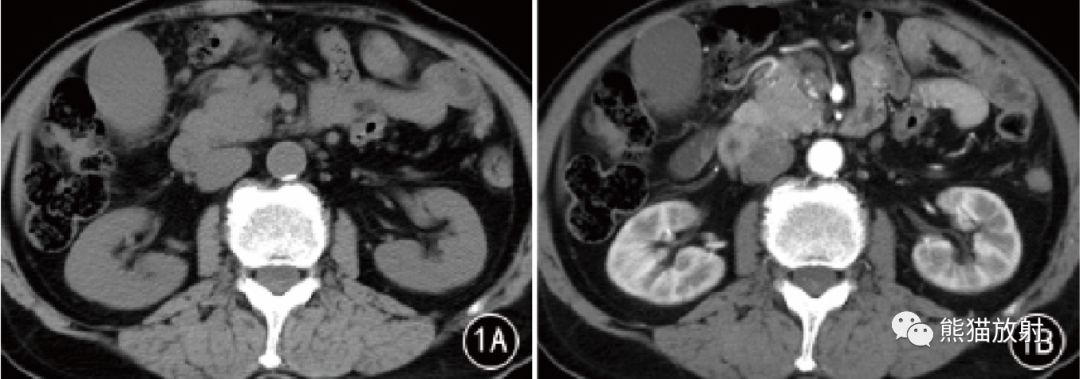

图1 男,75 岁。AIP 胰头部局灶性病变,CT平扫呈稍低密度,增强动脉期和门静脉期渐进性均匀强化。镜下见胰腺导管管壁增厚,周围炎性浸润和纤维化,闭塞性静脉炎( HE × 200)。